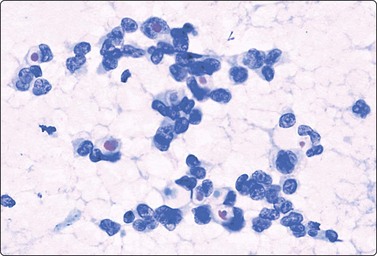

image image

Fig. 7.15 Regenerative epithelial atypia in mastitis

(A) Atypical, reactive/regenerating epithelial cells with a background of histiocytes, inflammatory cells and debris (MGG, HP); (B) Corresponding tissue section (H&E, IP).

There are four types of mastitis recognized; acute, chronic, granulomatous and non-specific.93 The diagnosis of acute mastitis and abscess presents no problems. Pregnancy is the most common association, but occasionally cysts become infected (often by coagulase-negative staphylococci). The entity of subareolar abscess is recognized separately (Fig. 7.16). Chronic mastitis may be the result of persistence of an acute mastitis, a reaction to retained secretion in fibrocystic disease or duct ectasia, or secondary to previous surgery.

Epithelial atypia can be worrying in some cases of mastitis (Fig. 7.17). Caution is advised in interpreting cytologic findings within the clinical context. However, open biopsy may be necessary for definitive diagnosis in rare cases.

Problems and differential diagnosis

Regenerative atypia of duct epithelium in an area of mastitis can look worrying and suspicious (Figs 7.15A and 7.17). In addition, the nuclei of reactive histiocytes may appear large and atypical, particularly in air-dried smears. False-positive diagnoses in cases of chronic mastitis and organizing fat necrosis have been reported. However, large numbers of both acute and chronic inflammatory cells are rarely seen in carcinoma. In medullary carcinoma with lymphocytic infiltration and in comedocarcinoma, in which lymphocytes and histiocytes are mixed with the carcinoma cells, the latter dominate and nuclear morphology is obviously malignant. The presence of necrotic cell debris should evoke a suspicion of malignancy.